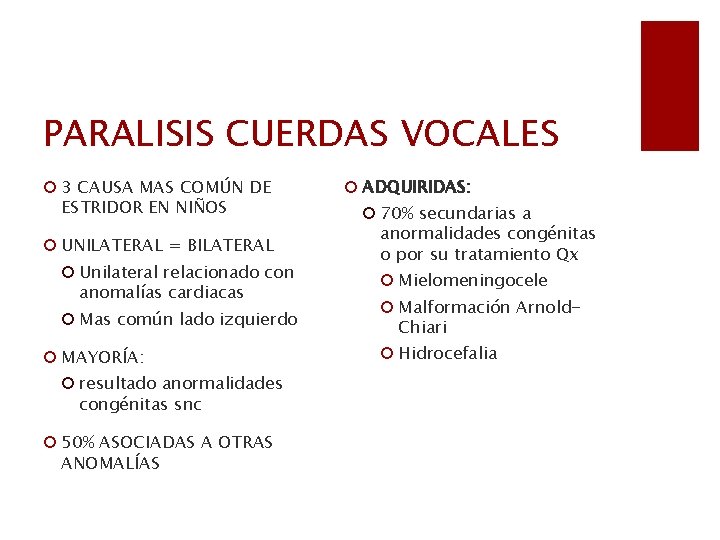

PARALISIS CUERDAS VOCALES ¡ 3 CAUSA MAS COMÚN DE ESTRIDOR EN NIÑOS ¡ UNILATERAL = BILATERAL ¡ Unilateral relacionado con anomalías cardiacas ¡ Mas común lado izquierdo ¡ MAYORÍA: ¡ resultado anormalidades congénitas snc ¡ 50% ASOCIADAS A OTRAS ANOMALÍAS ¡ ADQUIRIDAS: ¡ 70% secundarias a anormalidades congénitas o por su tratamiento Qx ¡ Mielomeningocele ¡ Malformación Arnold. Chiari ¡ Hidrocefalia